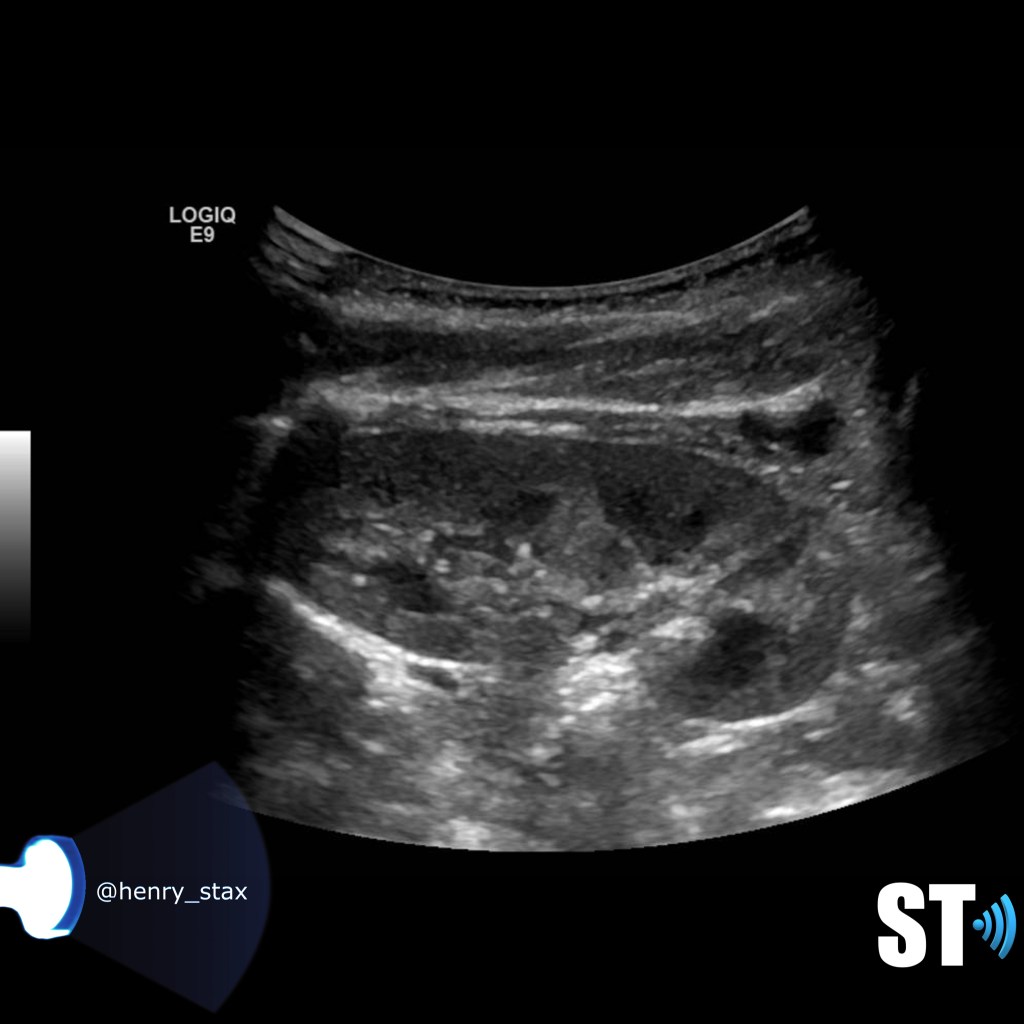

Acute pyelonephritis

Bacterial inflammatory disease of the kidney is commonly cause Eschericia coli. Most infections begin as UTI that ascends to the upper genitourinary system. the infection spreads from the renal pyramids into the renal cortex. The infection may be focal or diffuse. This condition usually presents with chills, fever, flank pain and laboratory findings of urinary infection.

Ultrasound may show an enlarged kidney with edema and increased echogenicity. You may also see a focal triangular area of altered echogenicity that displays reduced perfusion with color Doppler and power Doppler. If left untreated or inadequately treated that area can turn into an abscess.

An abscess will be well formed and distinct from the remainder of the renal parenchyma, it will be heterogeneous, complex appearance with mixed echoic and anechoic portions and no color doppler signal internally..

Once an abscess has formed drainage under ultrasound guidance can be performed. On subsequent imaging you notice some cortical thinning where the abscess was representing scarring.